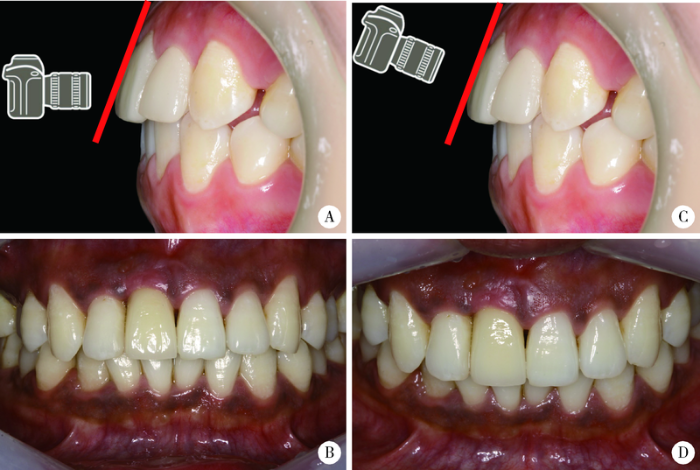

图2

前牙美学分析照片拍摄时要注意拍摄角度

Figure 2

Attention should be paid to the shooting angle when taking photos of anterior teeth for aesthetic analysis

A, the shooting angle is not perpendicular to the tooth surface; B, the photo cannot reflect the actual width-to-length ratio of the crown and the incisal edge curvature; C, the shooting angle is perpendicular to the tooth surface; D, the photo can reflect the actual width-to-length ratio of the crown and the incisal edge curvature.